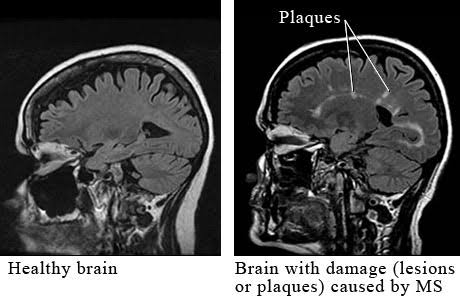

I’ve had the results from my MRI done a couple of weeks ago, there has been no change. Given the AHSCT is very much about halting progression, I am very happy to see that one of the main clinical indicators is showing no deterioration. This means that there has been no further attacking of my myelin sheath by my new, naive immune system. Repair of the myelin sheath is an area where a lot of research is being done right now, and I am watching with great interest.

There’s a couple of graphs and images I’ve posted before but here they are again, and how true they are.